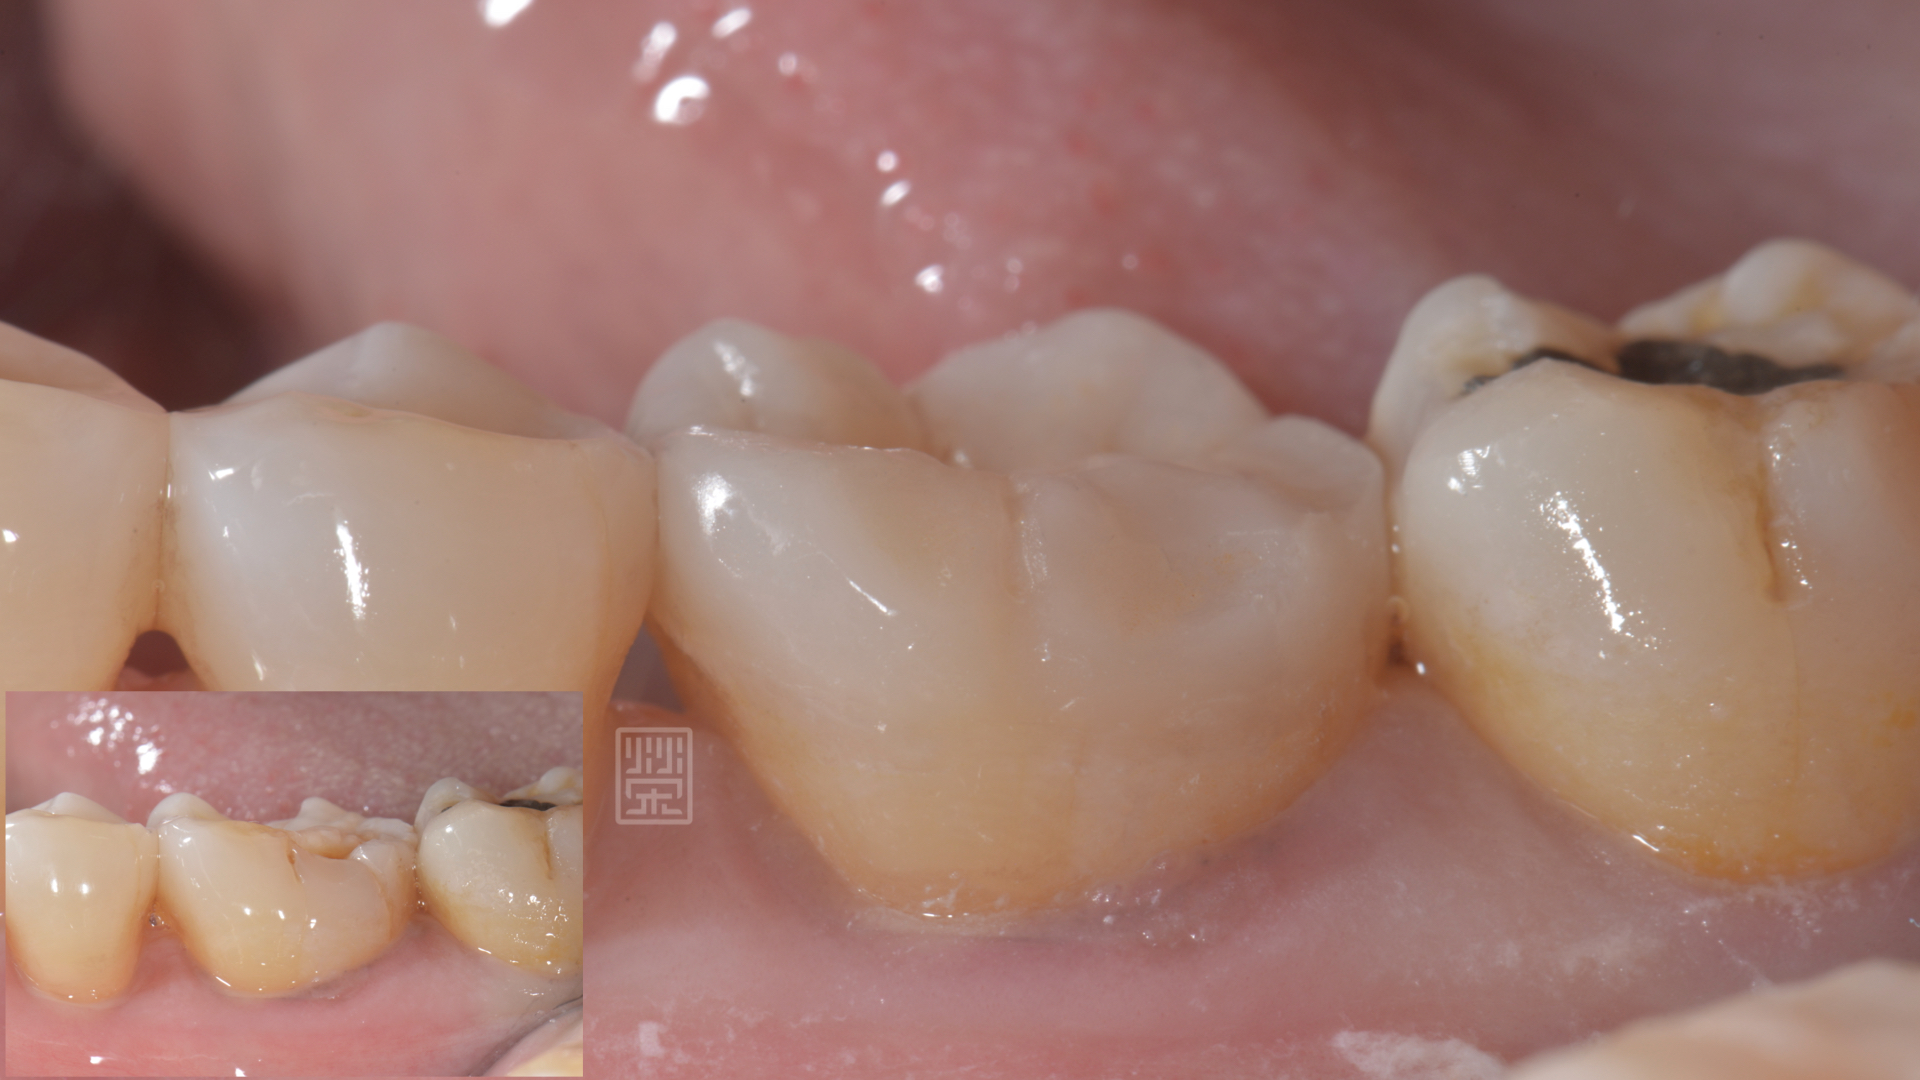

頰側有裂痕